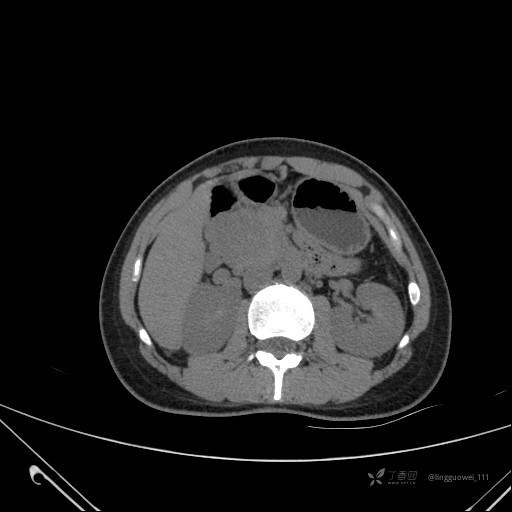

患者性别:女

患者年龄:28岁

主诉:体检发现胰腺病变,行 CT检查。

动脉期: